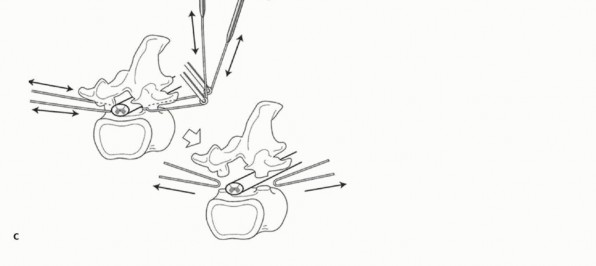

1. Introduction of the T-Saw Guide

To make an exit for the T-saw guide through the nerve root canal, the soft tissue attached to the inferior aspect of the pars interarticularis is dissected and removed using utmost care so as not to damage the corresponding nerve root. A C-curved malleable T-saw guide is then introduced through the intervertebral foramen in a cephalocaudal direction. In this procedure, the tip of the T-saw guide should be introduced along the medial cortex of the lamina and the pedicle so as not to injure the spinal cord and the nerve root(TECH FIG 2).

TECH FIG 2. A. Schematic diagram depicting introduction of the T-saw guide. B. A C-curved malleable guidewire is introduced through the right intervertebral foramen in a cephalocaudal direction.

After passing the T-saw guide, its tip at the exit of the nerve root canal can be found beneath the inferior border of the pars interarticularis. A T-saw is passed through the hole in the wire guide and is clamped with a T-saw holder at each end. The T-saw guide is removed, and tension on the T-saw is maintained.

2. Cutting the Pedicles and En Bloc Laminectomy

While tension is maintained, the T-saw is placed beneath the superior articular and transverse processes with a specially designed T-saw manipulator. With this procedure, the T-saw placed around the lamina is wrapped around the pedicle. With a reciprocating motion of the T-saw, the pedicles are cut, and then the whole posterior element of the spine (the spinous process, the superior and inferior articular processes, the transverse process, and the pedicle) is removed in one piece(TECH FIG 3). The cut surface of the pedicle is sealed with bone wax to reduce bleeding and to minimize contamination by tumor cells.

TECH FIG 3. A,B. Right pedicle is cut with a reciprocating motion of the T-saw. C. Schematic drawing of the pediculotomy.